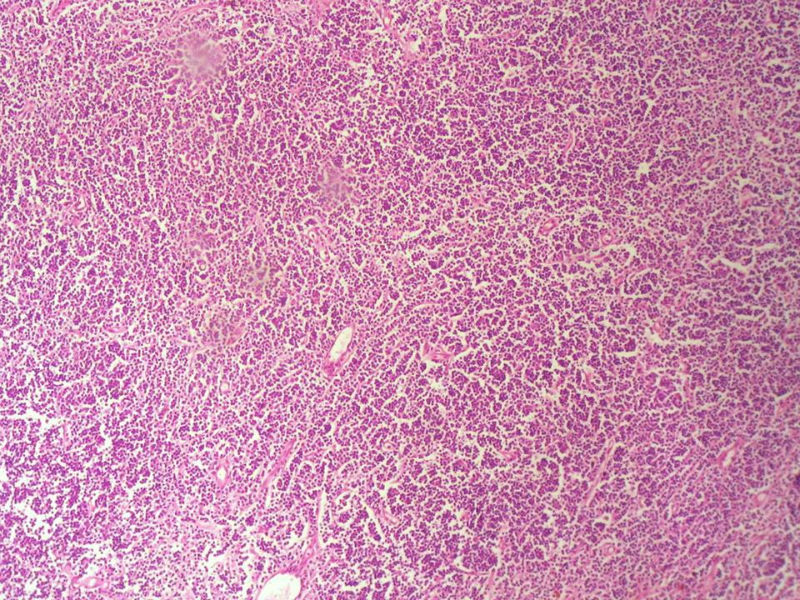

男,49岁,左眼睑球结膜下肿物2个月,手术切除。检查肿块3X2X2厘米,切面灰红色,质软。

HE:  1.MALT粘膜相关淋巴瘤:本例部位很特殊,位于“结膜下”,考虑MALT很合理;但本例镜下细胞形态很一致,诊断MALT是有难度的。

赞成以上专家的讨论,根绝病史,HE形态考虑小细胞病变,CD3、CD5散在+,还是倾向淋巴造血系统病变,CD20、CD79a阳性不明确,可以考虑复查,加做PAX-5,核阳性容易判断,另再加做鉴别其它小细胞肿瘤的抗体:CD99、CD43、CyclinD1、CK、CgA、Syn等,了解病史:骨髓、末梢血、肝、脾等。

淋巴样细胞。细胞形态单一,细胞小。主要鉴别:

1)粘膜相关淋巴组织淋巴瘤

2)小细胞性淋巴瘤/慢性淋巴细胞性白血病

3)套细胞淋巴瘤

形态结构与细胞大小,似不支持滤泡性淋巴瘤。

要多取材,标记鉴别假性淋巴瘤。

上级医院会诊意见:

CD20(+),Kappa(+),ki-67(+)>2%,Lambda(+),Pax-5(+),符合粘膜相关淋巴瘤。